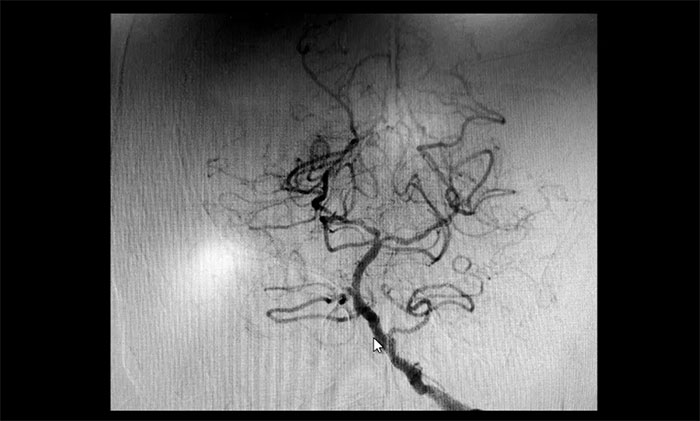

頸內(nèi)動(dòng)脈狹窄可分為輕度(<50%),中度(50%~69%)和重度(70%~99%),椎動(dòng)脈狹窄的判別標(biāo)準(zhǔn)與之相仿。DSA檢查示:患者雙側(cè)頸內(nèi)動(dòng)脈及左側(cè)椎動(dòng)脈存在重度狹窄,狹窄程度達(dá)到甚至超過(guò)90%,病情十分嚴(yán)重,遂立即收治入院。

▲ 雙側(cè)頸內(nèi)動(dòng)脈及左側(cè)椎動(dòng)脈重度狹窄